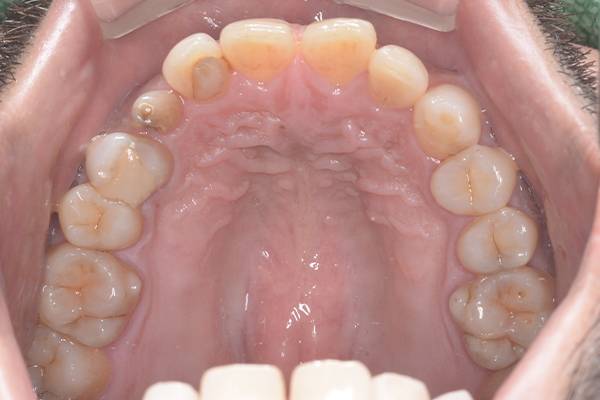

Case.03

インプラントの症例 インプラントの症例

治療前〜治療後のレントゲン写真

患者様の要望過去に治療したブリッジを外し咬み合わせの平面を整えて、被せ物や詰め物を綺麗にしたい。

治療期間10ヶ月

治療費用約1,600,000円

治療内容インプラント2本、アンカースクリューを用いた部分矯正、

セラミックによる補綴治療

治療のリスクセラミックの破折の

可能性